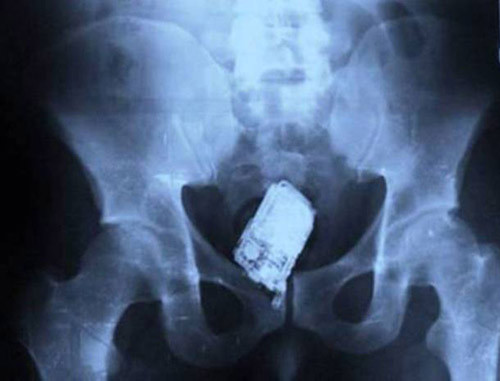

Chiếc điện thoại di động này được tìm thấy trong cơ thể một tù nhân tại San Salvador. Không muốn bị phát hiện dùng trộm điện thoại, anh ta đã tìm cách nuốt nó.